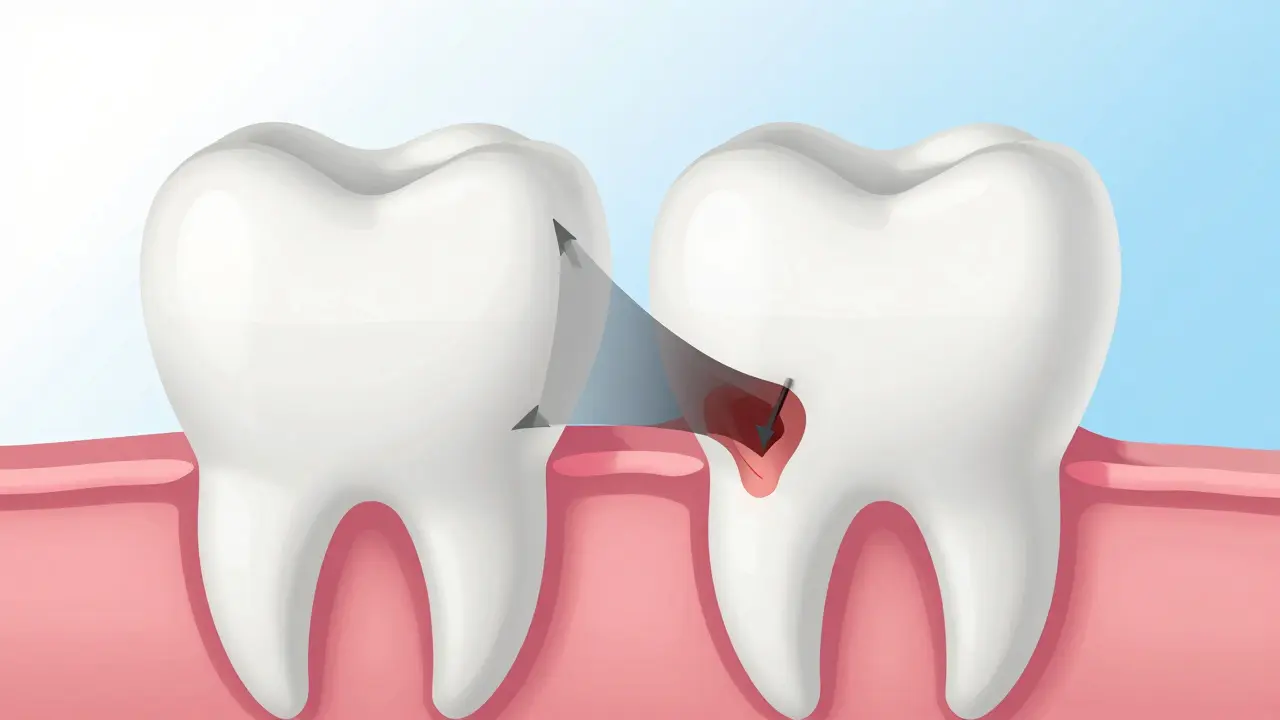

Průřez zubem s postupem karies z emalové vrstvy do dentinu, znázorněný tmavou klínovitou oblastí.